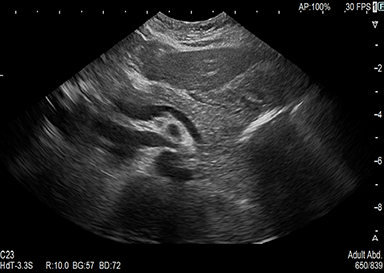

超音波検査とは

頸部(動静脈・甲状腺)、心臓、腹部(肝臓・胆のう・膵臓・脾臓・腎臓・膀胱・腹部大動脈等)、下肢(動脈・静脈)等が観察できる検査です。

高齢者でも無理なく行えます。病変の経過観察、早期発見としたスクリーニング検査などが行えます。